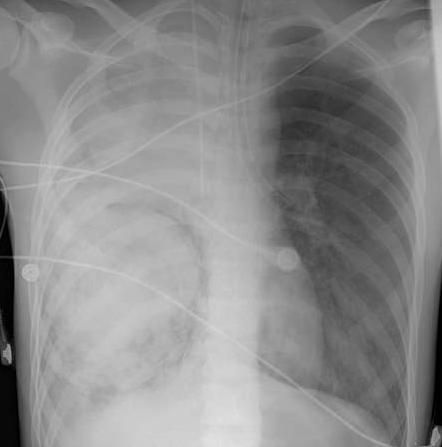

The patient's hemoglobin level was 7.1 g/dL. His symptoms progressively worsened to the extent that he required volume resuscitation, packed red blood cell transfusion, and intubation. A chest radiograph showed a dense infiltrate in the right lower and middle lobes and increased opacity of the right upper lobe (Figure 1). Malignancy, necrotizing pneumonia, and arteriovenous malformation were all considered.

Figure 1 – A dense infiltrate can be seen in the right lower and middle lobes (with a circular rim around it) in this chest radiograph. Also, increased opacity is noted in the right upper lobe.